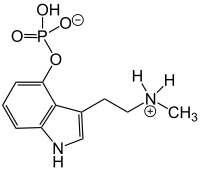

| Aeruginascin | Fungi | 4-OPO3H2 | (CH3)3 | [3-[2-(trimethylazaniumyl)ethyl]-1H-indol-4-yl] hydrogen phosphate | 114264-95-8 | |